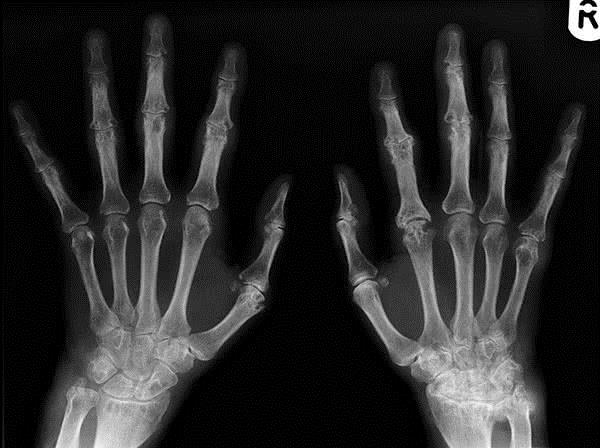

К главным симптомам ревматоидного полиартрита относятся суставные боли и деформации мелких суставов. Часто поражаются мелкие суставы кистей рук и пальцев. Для данной патологии характерна симметричность поражения суставов. В зависимости от количества вовлеченных суставов, врачи определяют стадию и вариант течения заболевания.

Сначала отметим, что в 2/3 случаев заболевание развивается с поражением сразу многих суставов, как правило, мелких (кистей и стоп, лучезапястных). В этом случае ставится диагноз ревматоидного полиартрита. Если же поражены, например, только колени или локти, диагноз звучит как олигоартрит – 1/3 всех случаев.

В случае наличия симптомов полиартрита на протяжении одного года и более длительного времени следует проводить рентгенографию рук и ступней. Своевременная диагностика полиартрита имеет очень большое значение. Ведь только при правильной и оперативной терапии больной сможет упредить появление повреждений суставов и иных серьезных нарушений.